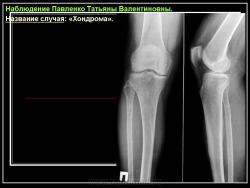

Хондрома (солитарная энхондрома, центральная хондрома) - доброкачественная опухоль из гиалинового хряща, расположенная в костномозговом канале кости. Обследовали 23 мужчины и 18 женщин с хондромой кости.

Рентгенологическая картина хондромы представляет четко очерченный опухолевый узел. Очаги минерализации в хондромах выглядят достаточно характерно и представлены очаговыми, глыбчатыми или кольцевидными , арочными отложениями извести. Полного разрушения кортикального слоя трубчатой кости с выходом опухолевых масс в мягкие ткани не наблюдается.

Энхондроматоз